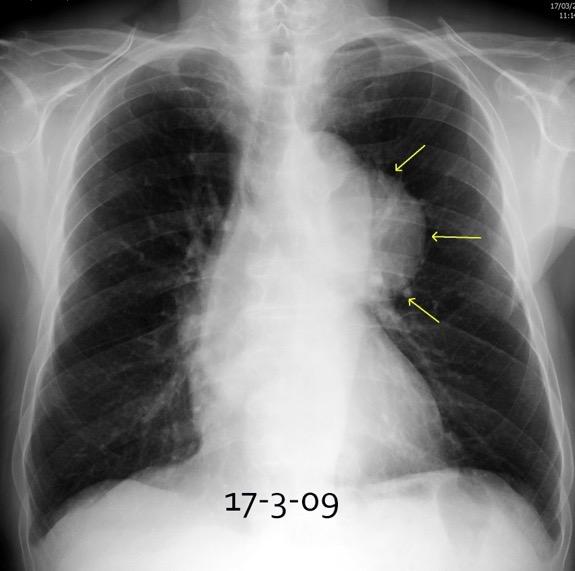

30 años

Borramiento de la banda PARA-aórtica por AdenoCa. de LII, no visible en 2005

Colapso de LII. TC: secreciones bronquiales.

Endoscopia tapón mucopurulento extraído

Borramiento parcial por Ca. epidermoide.